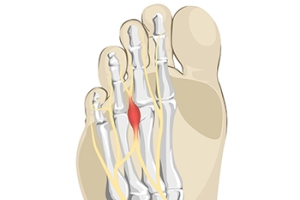

Morton's neuroma is a painful foot condition that commonly affects the areas between the second and third or third and fourth toe, although other areas of the foot are also susceptible. Morton’s neuroma is caused by an inflamed nerve in the foot that is being squeezed and aggravated by surrounding bones.

Morton's Neuroma, also called Intermetatarsal Neuroma or Plantar Neuroma, is a condition that affects the nerves of the feet, usually the area between the third and fourth toe. Neuroma refers to a benign growth that can occur in different parts of the body. Morton's Neuroma strictly affects the feet. This condition causes the tissue around the nerves that lead to the toes becoming thick, causing pain in the ball of the foot.